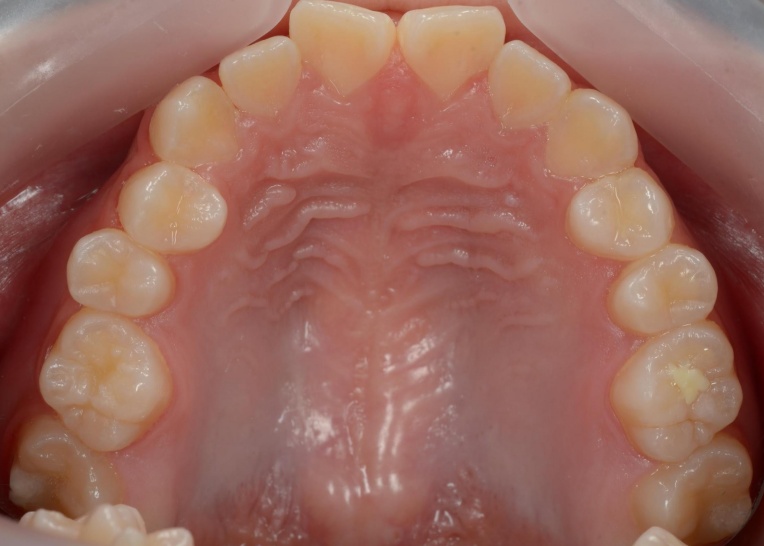

「前歯が噛み合わないので治したい」とご相談いただきました。 |

拝見したところ、重度の開咬(かいこう)が認められました。 |

見た目と噛む機能の両方を改善するため、矯正治療を提案し、同意いただきました。 |